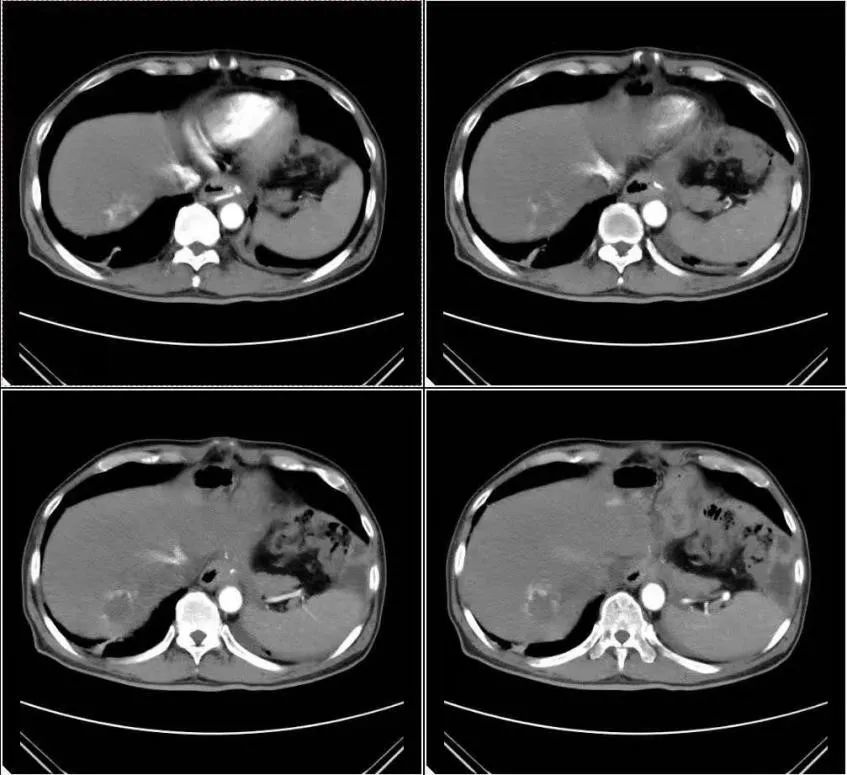

其实,在整个项目的实施过程中,有几个受试者的不良反应是相对来说比较大的,我总是跟患者沟通,或者跟他的主治医生沟通,希望这些患者能够坚持下来。其中也有一些治疗效果非常好的病例。我印象比较深刻的是一个68岁的男性患者,在胃癌手术过程中清扫了40多个淋巴结,其中有19枚淋巴结都发生了转移。这样一个相对晚期的患者,按照以往的经验,术后短时间内可能会发生复发转移,甚至是死亡。但是这位患者,自愿入组了我们的临床试验,配合治疗。截至4月底的最新随访,该患者服用阿帕替尼时长已达到478天,并且到目前为止,该患者的生活质量良好!正是由于这么多的患者从这个临床试验中获益,我们才更有动力将这个项目坚持下去,也能让我们更多地去与外科医生,内科医生去交流,去学习,让他们也对这个方案,对这个临床研究充满信心!